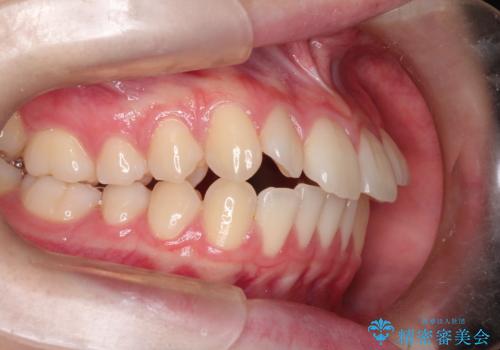

【インビザライン】前歯のガタガタをなおしたい

- 前歯のガタガタを主訴に来院されました。

開咬ぎみであったため、しっかりと前歯が噛むように計画を立てて治療をおこないました。

仕上がりも良く、患者様にも満足していただきました。

インビザラインは前歯を噛ませるような開咬の治療も得意としています。